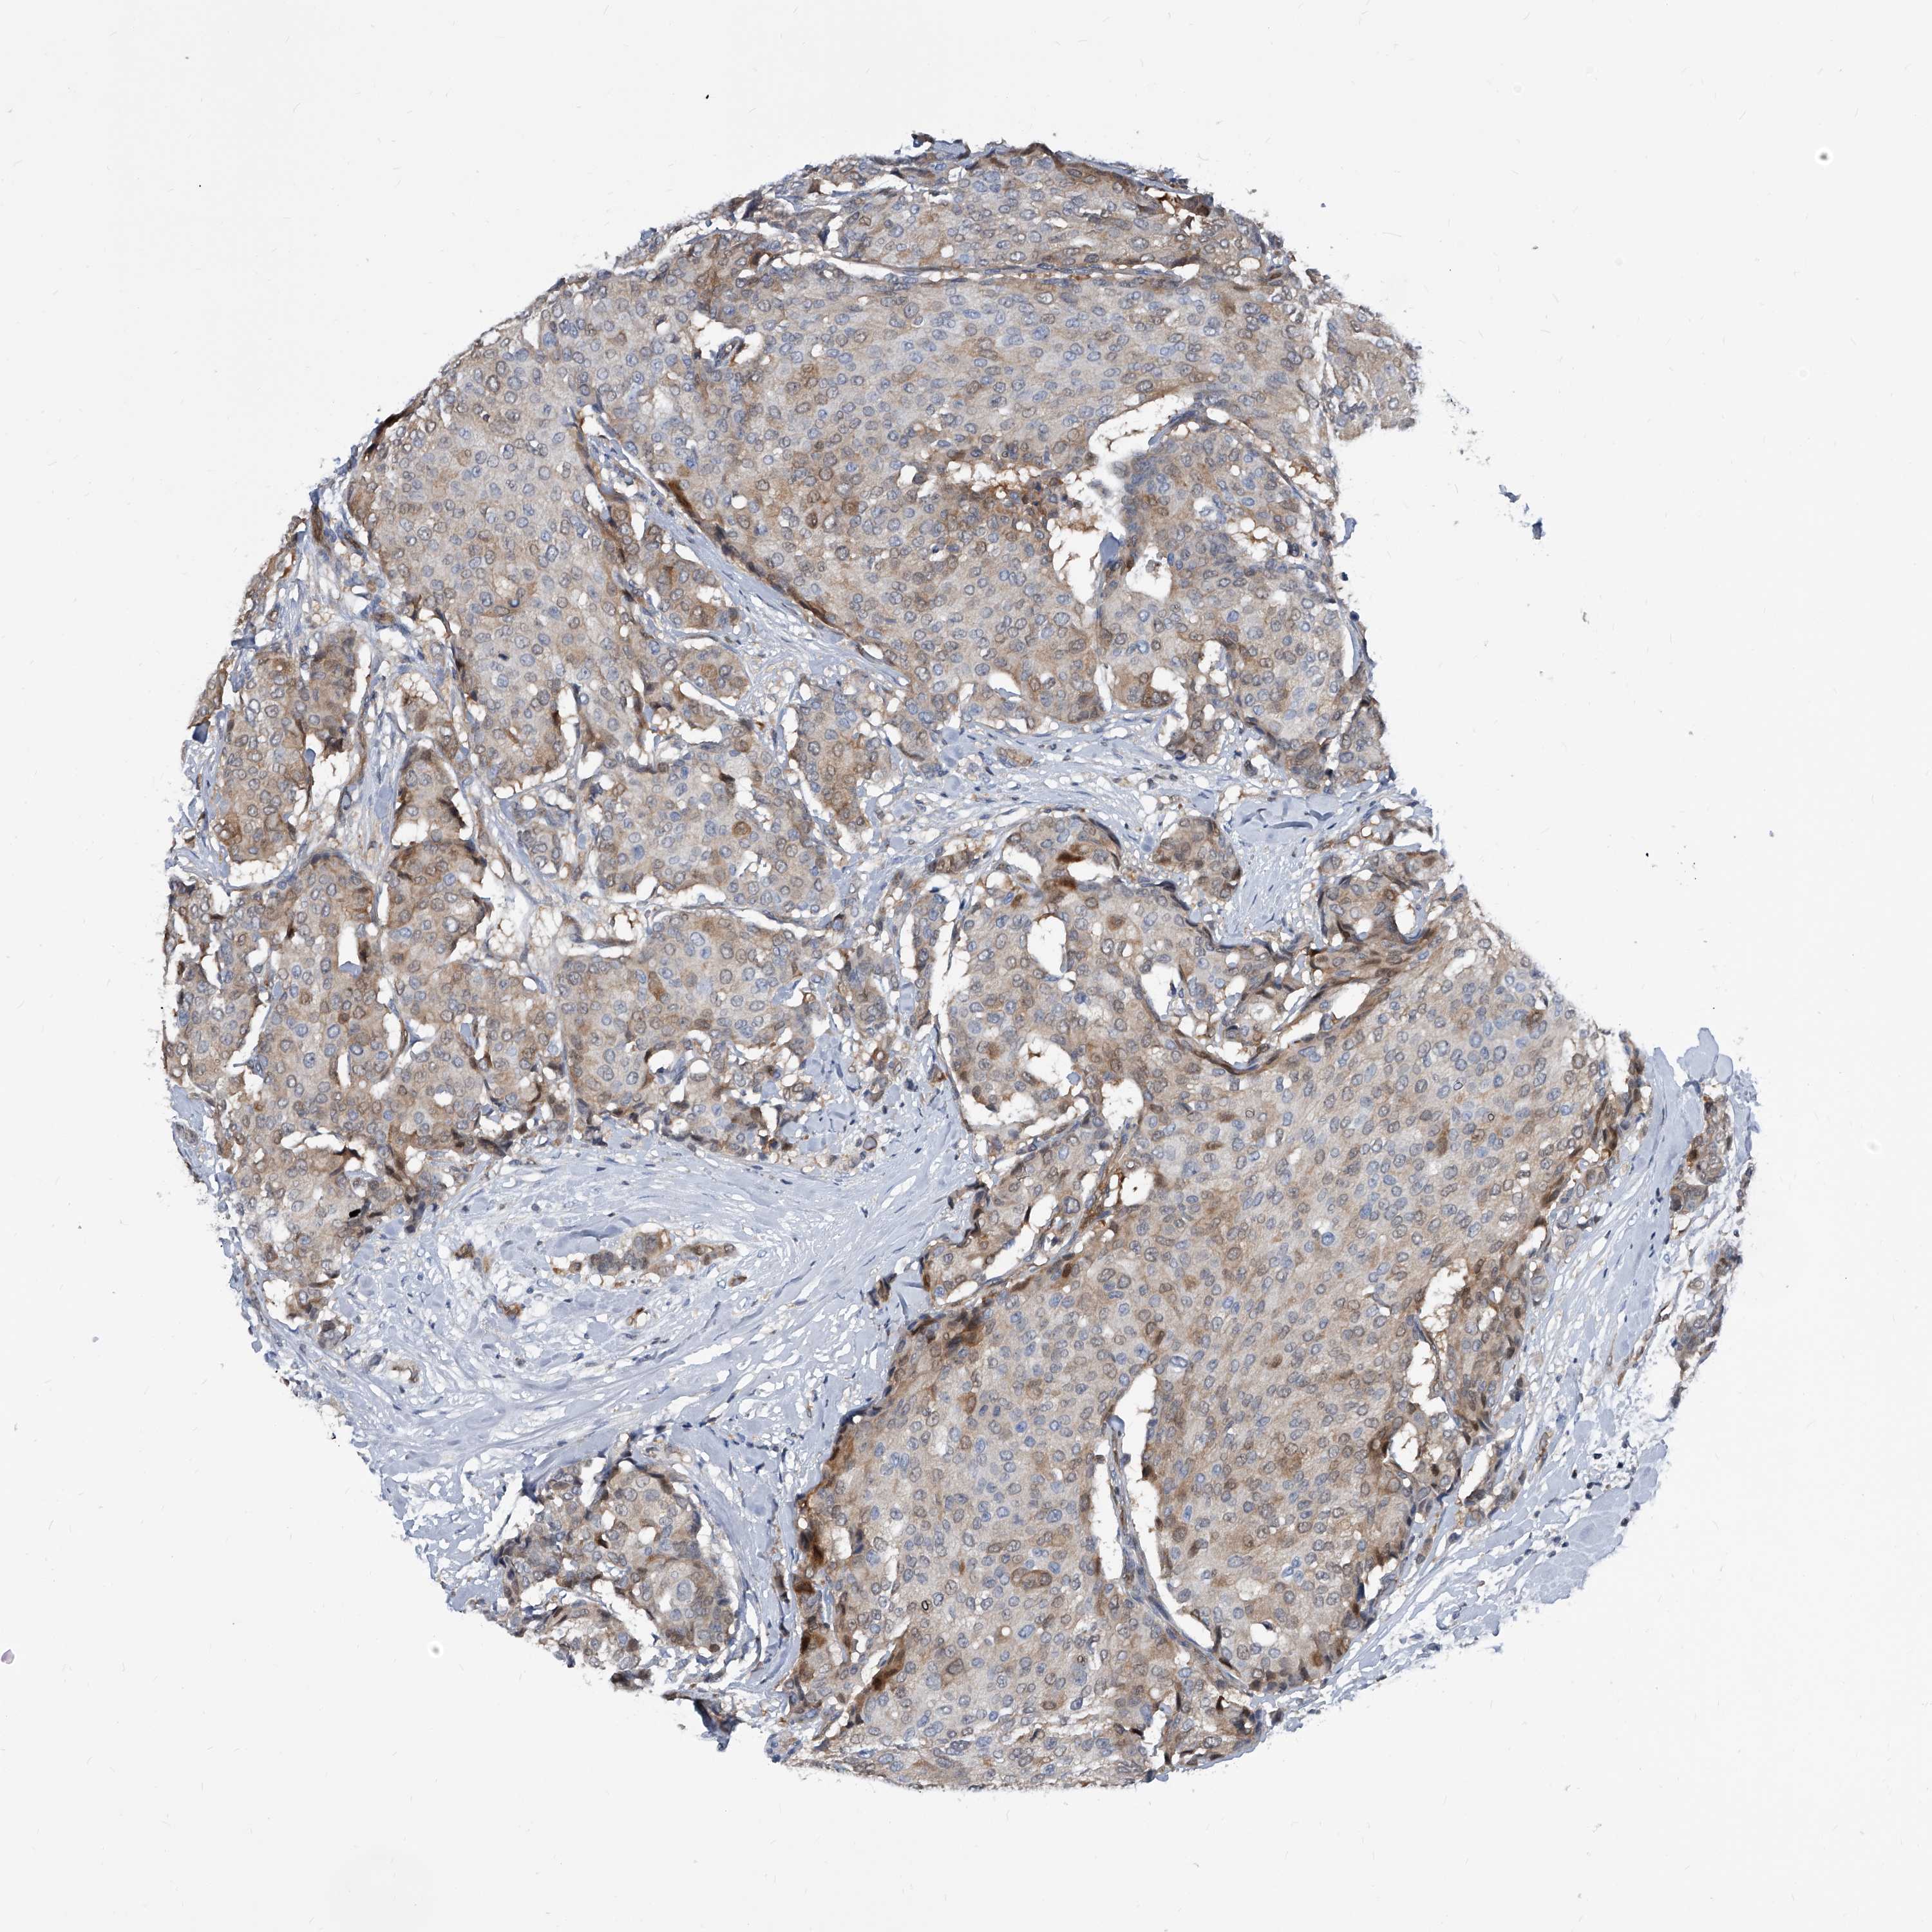

CANCER BREAST CANCER Show tissue menu

BRCA TCGA BRCA VALIDATION PROTEIN EXPRESSION

Breast cancer

Human cancer

MAP2K6 is potential prognostic, high expression is favorable in Breast Invasive Carcinoma (TCGA)